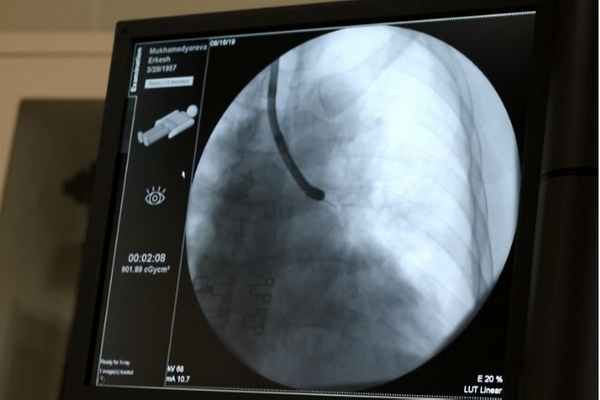

А теперь представьте себя в операционной: с помощью эндоскопа продвигаемся через просветы бронхов - сквозь трубку диаметром в 6 миллиметров проводим еще более тонкие иглы для выполнения манипуляции в легком и в лимфоузлах. При этом поле нашего действия (сегмент легкого, пределы предполагаемого образования) мы перед этим подробно изучили благодаря снимку компьютерной томографии пациента, потому знаем, в какой области нам необходимо действовать. Но для точности этого не достаточно: навигатором во время самой манипуляции нам служит рентген – по нему мы видим, как и в каком направлении движутся наши инструменты в самом легком в режиме «прямого эфира»: на экране мы видим картину легкого, благодаря которому управляем всем процессом изнутри.